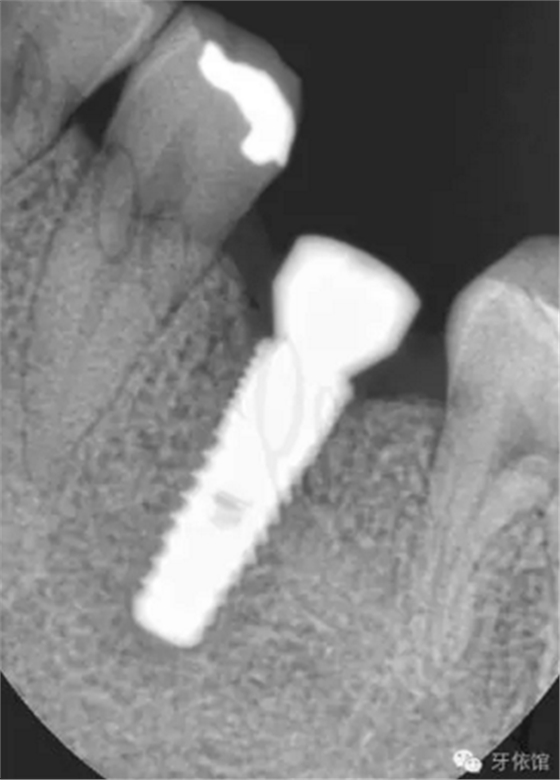

術(shù)后三個月的X光片。

連接印模帽后拍x光片,檢查印模帽與種植體之間是否緊密相連。

再將烤瓷冠就位,拍X光片,檢查烤瓷牙與基臺之間是否密貼。